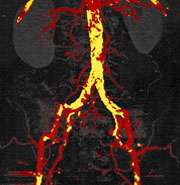

dual energy after bone removal

CT angiogram after automated bone removal displays aorta and iliac artery (red). Calcified plaque (yellow) limits evaluation of vessel stenosis.